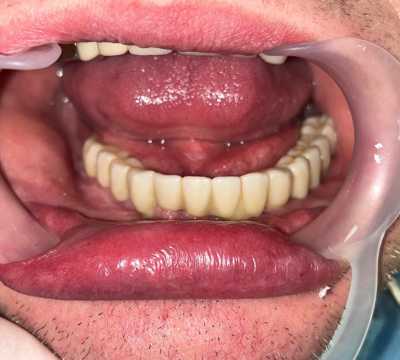

Cazul 70

All on 6, implanturi orale speciale pterigoide

Cazul 70: All on 6

Imaginile sunt prezentate în ordinea evoluției tratamentului, de la situația inițială la rezultatul final.